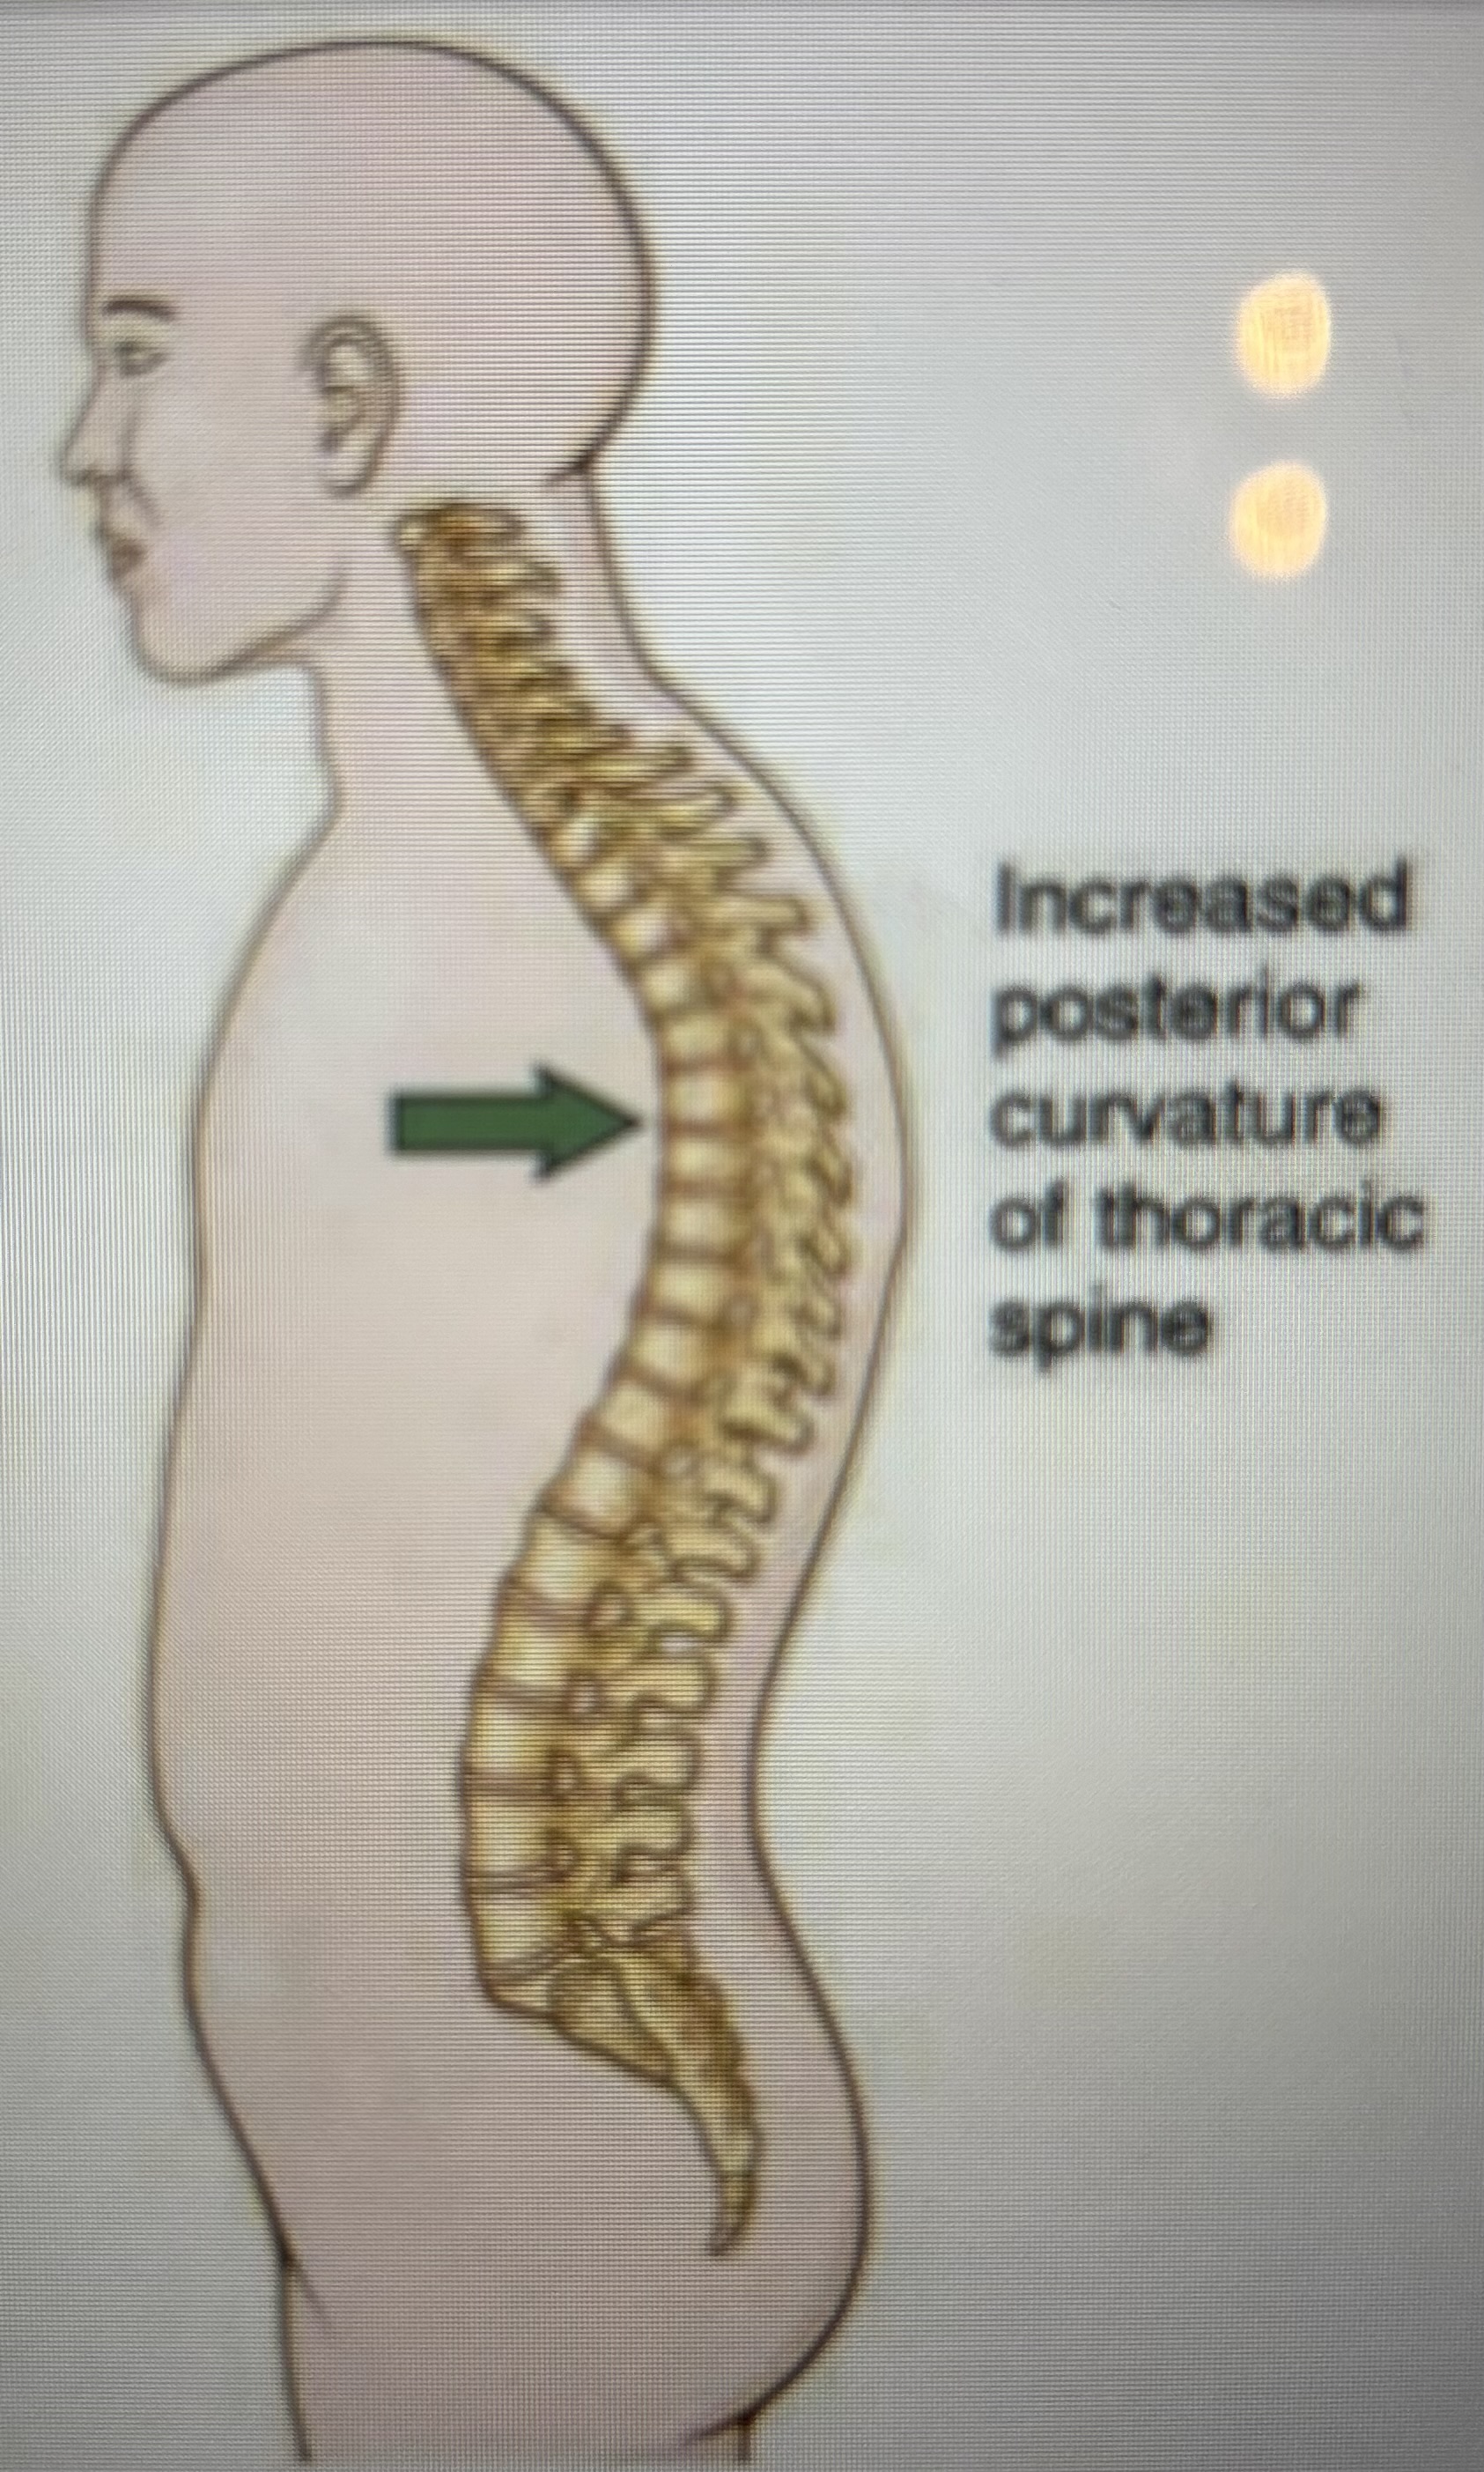

ROM

range of motion

kyphosis

increased posterior curvature of the thoracic spine

What is this spinal curvature?

Normal

What is this spinal curvature?

Lordosis

What is this spinal curvature?

Kyphosis